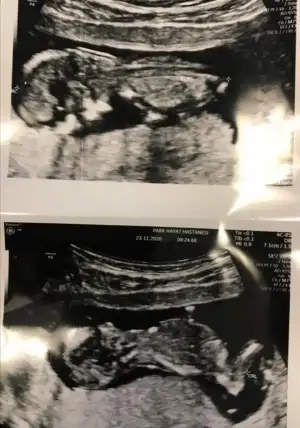

Kız gibi geldi nubu banaMerhabalar, benim de usg tam 12+0 haftalık, dr net konuşmamakla birlikte erkek gibi ama kesin bir şey demeyeyim dediyorumlarsanız çok sevinirim

USG net değil gördüğüm nub ise erkek sanki kaç haftalık USG

12 haftalıkUSG net değil gördüğüm nub ise erkek sanki kaç haftalık USG